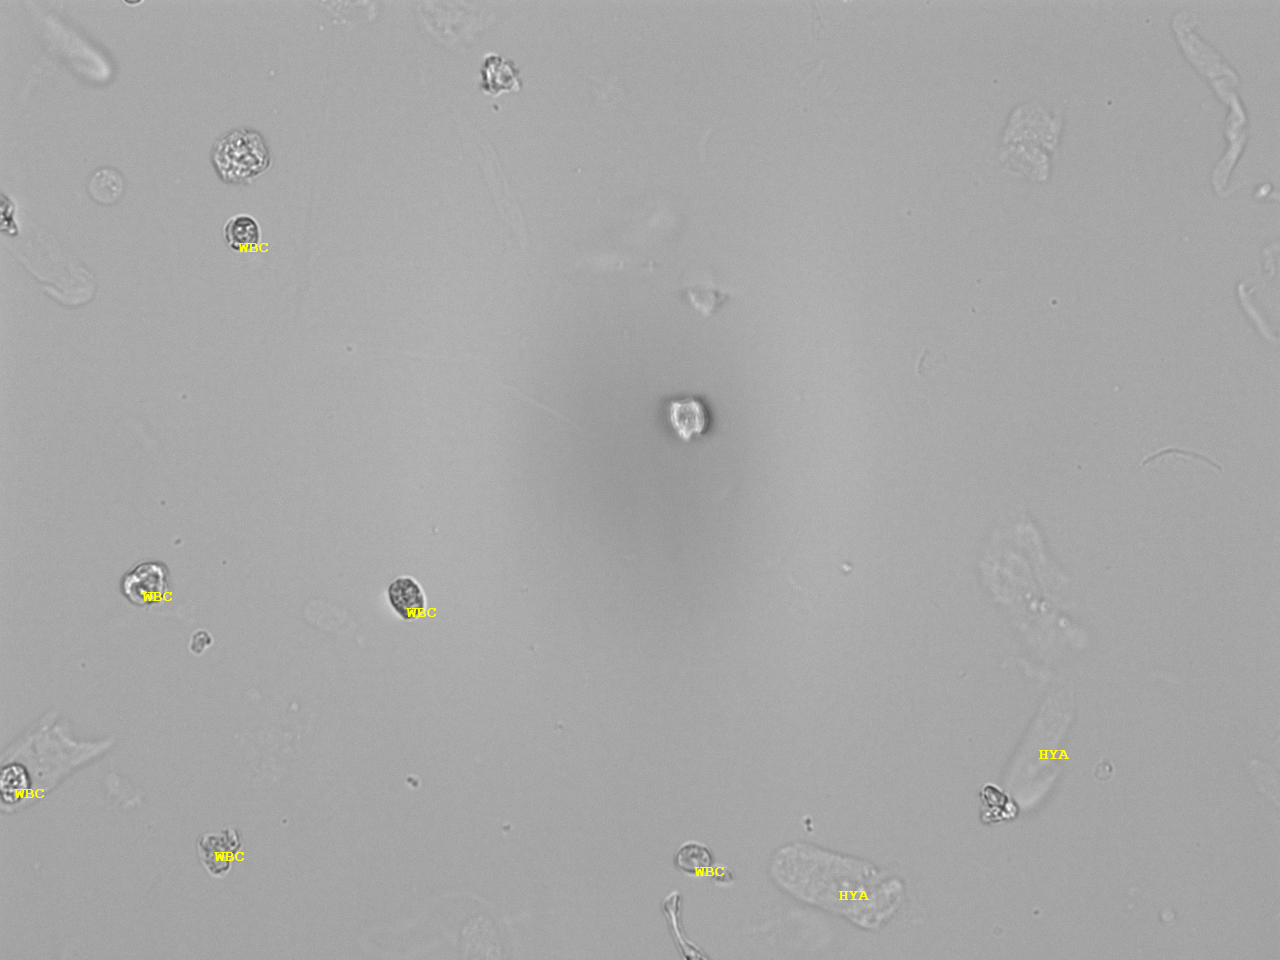

Urin-Feature: hyaline Zylinder